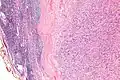

Low mag.

IPMs are diagnosed by examination of the tissue by a pathologist. They have a rim of peripheral lymphoid tissue (remnant of a lymph node) and consist of spindle cells with nuclear palisading. Red blood cell extravasation is common and blood vessels surrounded by collagen with (fine) peripheral spokes (amianthoid fibers) are usually seen.[2]

Immunostains for smooth muscle actin and cyclin D1 are characteristically positive. The main histologic differential diagnosis is schwannoma.